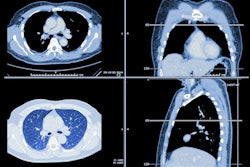

A 37-year-old man presented to the emergency department with cough and fever. An immediate CT scan was performed due to suspected pulmonary COVID-19 manifestation. Left: The axial minimum intensity projection (MinIP) reconstruction shows focal subtle ground-glass opacity in the left lower lung lobe (arrowhead) suspicious for early-stage pulmonary COVID-19, which was missed on axial multiplanar reformat series (Right) by 6/6 readers in this study. Real-time reverse transcription polymerase chain reaction confirmed severe acute respiratory syndrome coronavirus 2 infection. All figures courtesy of EJR and Dr. Christian Booz and colleagues.Some studies suggest that chest CT is more sensitive when it comes to diagnosing COVID-19 than reverse transcription polymerase chain reaction (RT-PCR) testing; this sensitivity is due to the modality's ability to identify ground-glass opacity, a key indicator of the disease. But standard transverse CT reconstructions and MPRs can miss ground-glass opacities due to overlay by vascular structures -- and that's bad news for patients, the team wrote.